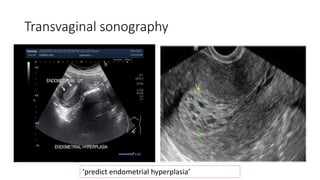

Transvaginal sonography

‘predict endometrial hyperplasia’

 postmenopausal bleeding with endometrial thickness >4mm(TVS)